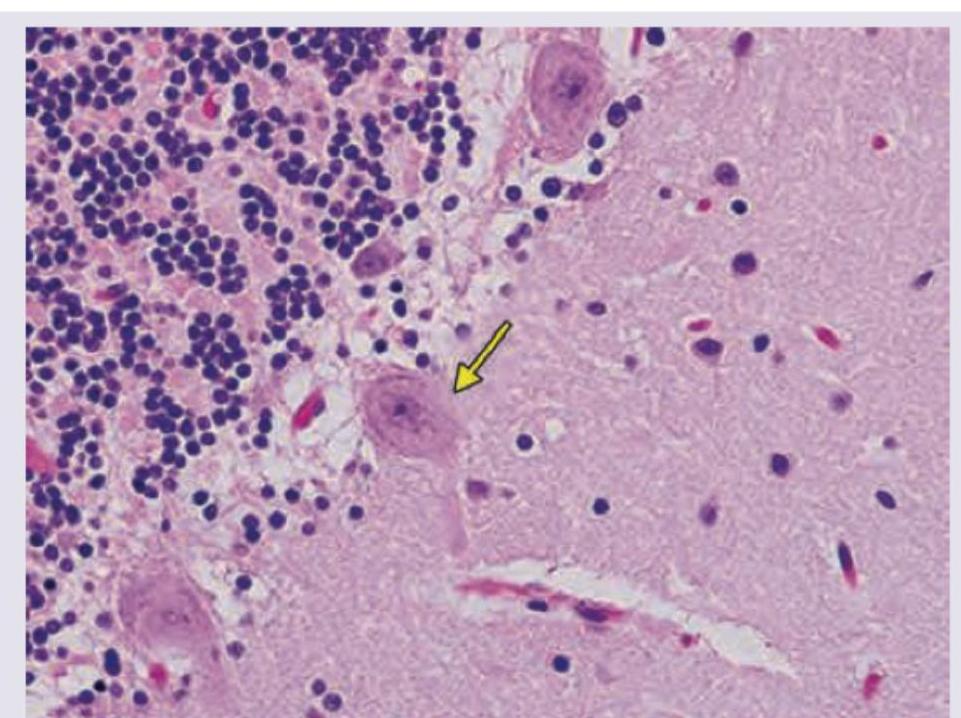

In the given slide of cerebellum, the marked cell is inhibitory to?

Explanation: ***Deep nuclei of cerebellum*** - The image shows a **Purkinje cell** (large, flask-shaped neuron with a prominent nucleolus, indicated by the arrow) located in the cerebellum. - Purkinje cells are the sole output neurons of the cerebellar cortex and exert an **inhibitory (GABAergic)** effect primarily on the **deep cerebellar nuclei.** *Vestibular nuclei* - While Purkinje cells of the **flocculonodular lobe and vermis** project to the vestibular nuclei, the primary and most direct inhibitory target discussed in the general context of Purkinje cell output are the deep cerebellar nuclei. - The Vestibular nuclei receive input from the cerebellum, but are not the sole or primary direct targets of all Purkinje cells. *Anterior horn of spinal cord* - The anterior horn of the spinal cord contains **motor neurons** and interneurons involved in motor control, but it does not receive direct innervation from Purkinje cells. - Cerebellar output influences spinal cord activity indirectly via relays in the brainstem and other motor control centers. *Basal ganglia* - The basal ganglia are subcortical nuclei involved in motor control and learning, forming a distinct neural circuit separate from the cerebellum. - There are **no direct inhibitory projections** from cerebellar Purkinje cells to the basal ganglia.